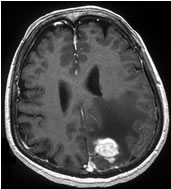

聴神経腫瘍

ガンマナイフの良い適応のひとつで、10年以上経過しても90%以上の症例で腫瘍制御が可能です。

左:ガンマナイフ時 中:5年後 右:10年後